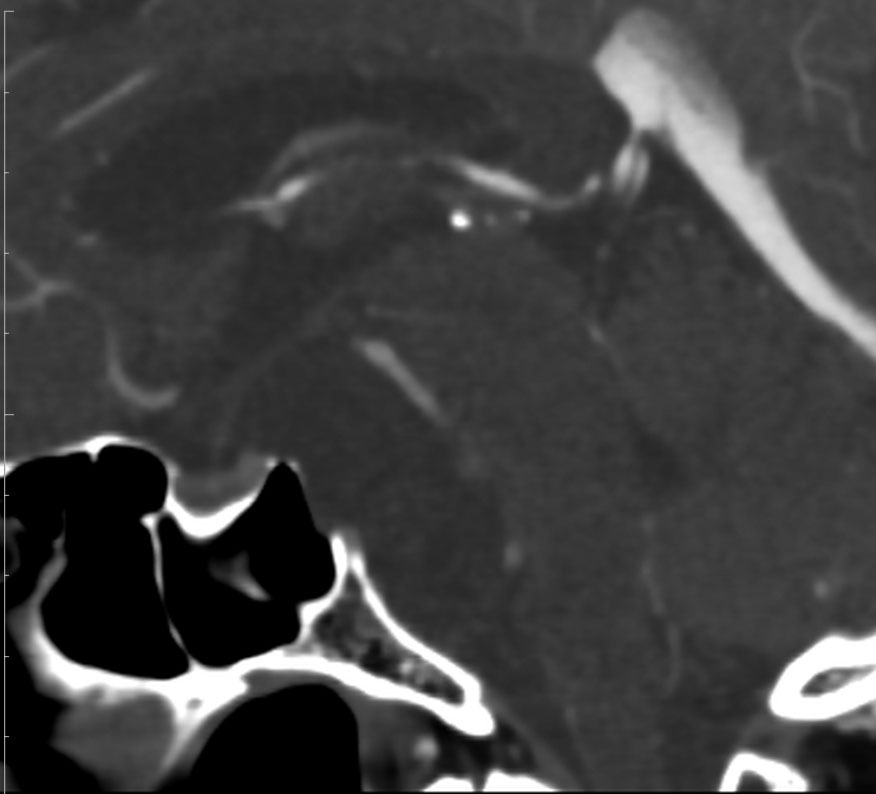

CTでは,斜台から左蝶形骨にかけて不規則な骨破壊像がみられます。

MRI T2強調画像(左)では等信号から高信号のまだらな境界が不明瞭な腫瘍が斜台から左海綿静脈洞内に浸潤しているのがみられます。T1強調ガドリニウム増強では,腫瘍がまだらに増強されています。トルコ鞍から鞍上部に伸び,視交差を侵し第3脳室底まで伸展しています。脊索腫が硬膜内に浸潤して神経組織と癒着することは珍しいことではありません。